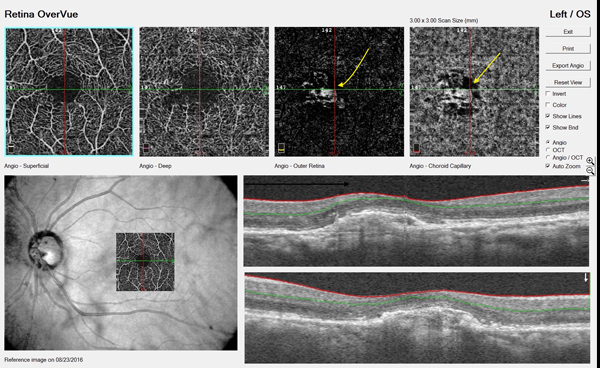

OCTA is a relatively new technology for imaging the retina and the retinal and choroidal vasculature. Currently, the »Cirrus 5000 Angioplex (Carl Zeiss Meditec) and the »AngioVue (Optovue) offer OCTA; similar platforms from Topcon and Heidelberg Engineering will soon be available in the United States. CNV can be detected directly with OCTA, giving clinicians a chance for early diagnosis of exudative AMD (Figure 3).5

Figure 3. OCTA of a patient with AMD. The yellow arrows indicate evidence of choroidal neovascular membrane.